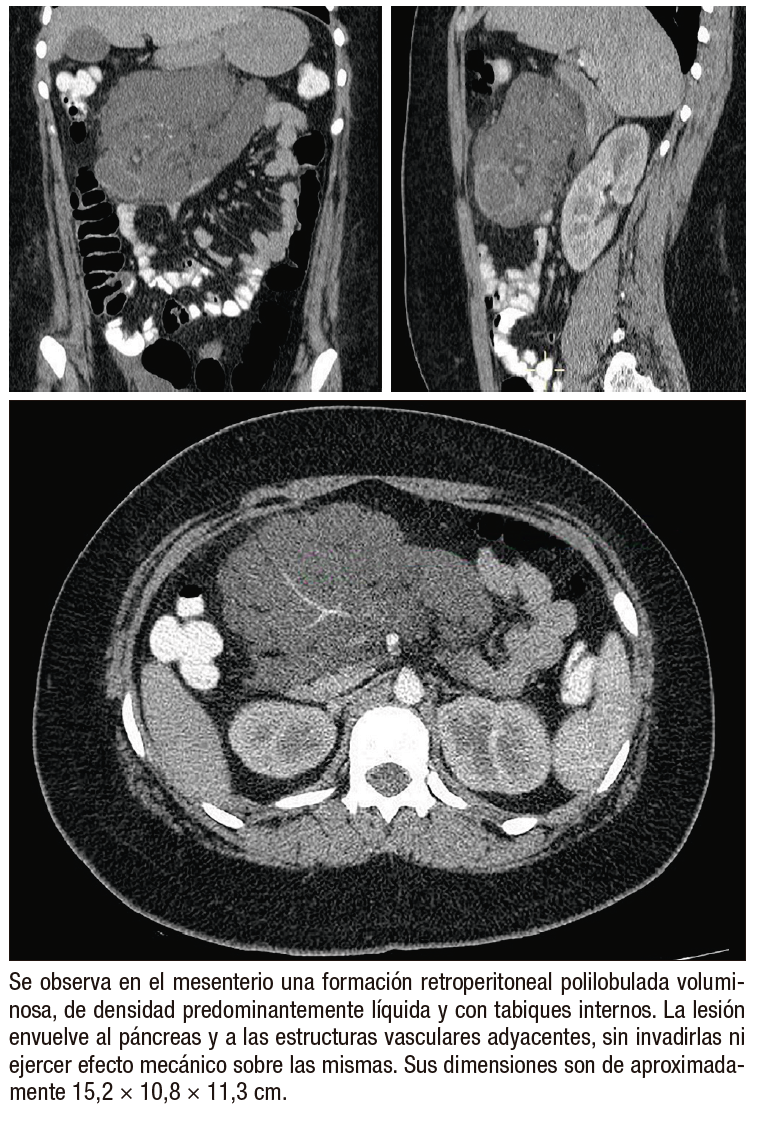

Figura 1. Tomografía computada multidetector con contraste endovenoso

En la TCMD, el LQR suele manifestarse como una masa quística multiseptada de gran tamaño, con paredes delgadas que pueden realzar tras la administración de contraste (Figura 1). Presenta una densidad homogénea, con valores de atenuación que varían desde líquido hasta grasa: atenuación negativa cuando el contenido es quiloso y alta atenuación cuando el contenido es hemorrágico, pudiendo simular una masa sólida. Debido a su tamaño, suelen cruzar los compartimentos anatómicos. En raras ocasiones presentan calcificación de la pared. Por otro lado, la RM es altamente sensible y útil para demostrar la naturaleza quística multiseptada de estas lesiones. El LQR se caracteriza por presentar hiperintensidad en secuencias ponderadas en T2 e hipointensidad en ponderaciones T1 (Figura 2).